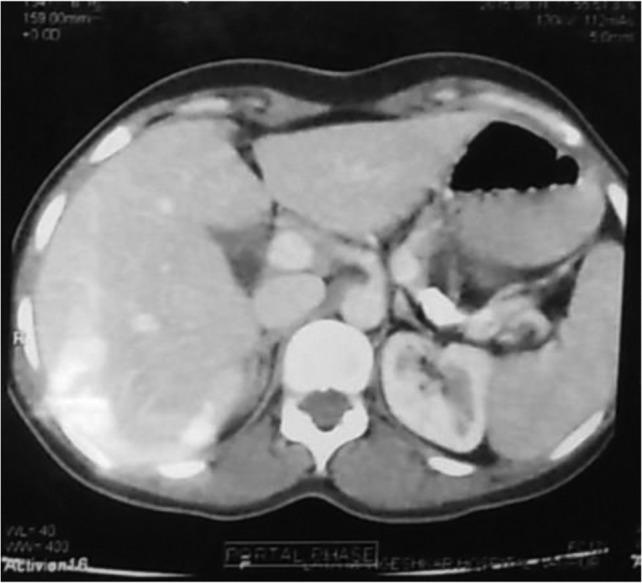

Acute obstructive suppurative pancreatic ductitis (AOSPD) is a rare complication of chronic pancreatitis that has been described in only seven previous case reports since 1995. We report a case of a 33-year-old female a known case of chronic pancreatitis with computed tomography suggestive of dilated main pancreatic duct with multiple calcifications. On exploration, pancreatic duct aspiration revealed frank pus. Pus was drained after opening the pancreatic duct and longitudinal pancreaticojejunostomy was done. Patient was relieved of her symptoms after surgery. In conclusion, AOSPD should be considered in long standing cases of chronic pancreatitis. AOSPD appears to respond quickly after drainage procedure like longitudinal pancreaticojejunostomy and should be considered the treatment of choice.

急性梗阻性化脓性胰管炎(AOSPD)是慢性胰腺炎的一种罕见并发症,自1995年以来仅有7例先前的病例报告对此进行过描述。我们报告一例33岁女性病例,该患者为已知的慢性胰腺炎患者,计算机断层扫描显示主胰管扩张并伴有多处钙化。术中探查时,胰管抽吸发现有脓性液体。打开胰管后引流出脓液,并进行了纵行胰管空肠吻合术。患者术后症状缓解。总之,对于长期存在的慢性胰腺炎病例应考虑AOSPD。AOSPD在纵行胰管空肠吻合术等引流手术后似乎反应迅速,应被视为首选治疗方法。